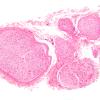

1A1 (Case 1) H&E 10X

1A1 (Case 1) Image_14920 10X